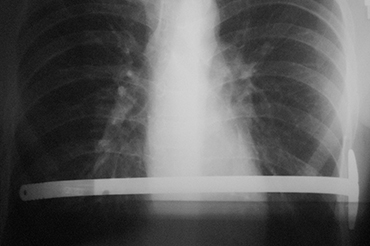

Pectus Excavatum